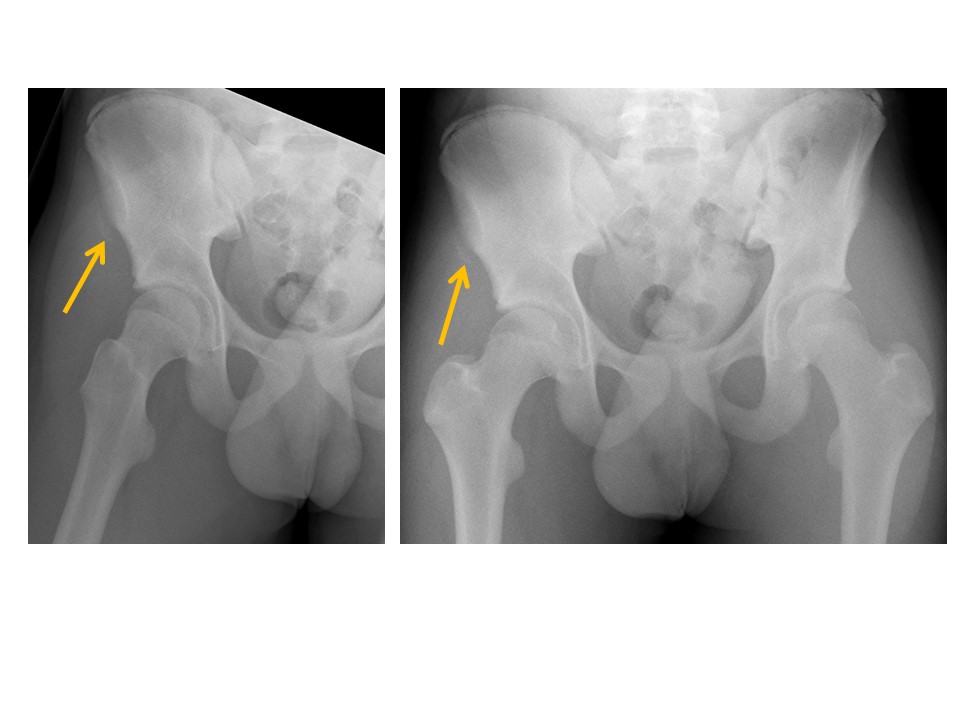

The proximal femoral physes are widened or abnormally smooth or irregular in contour. [Yes/No]

Klein lines asymmetrically cross the femoral epiphyses or there is displacement of the femoral epiphyses with respect to the femoral necks. [Yes/No]